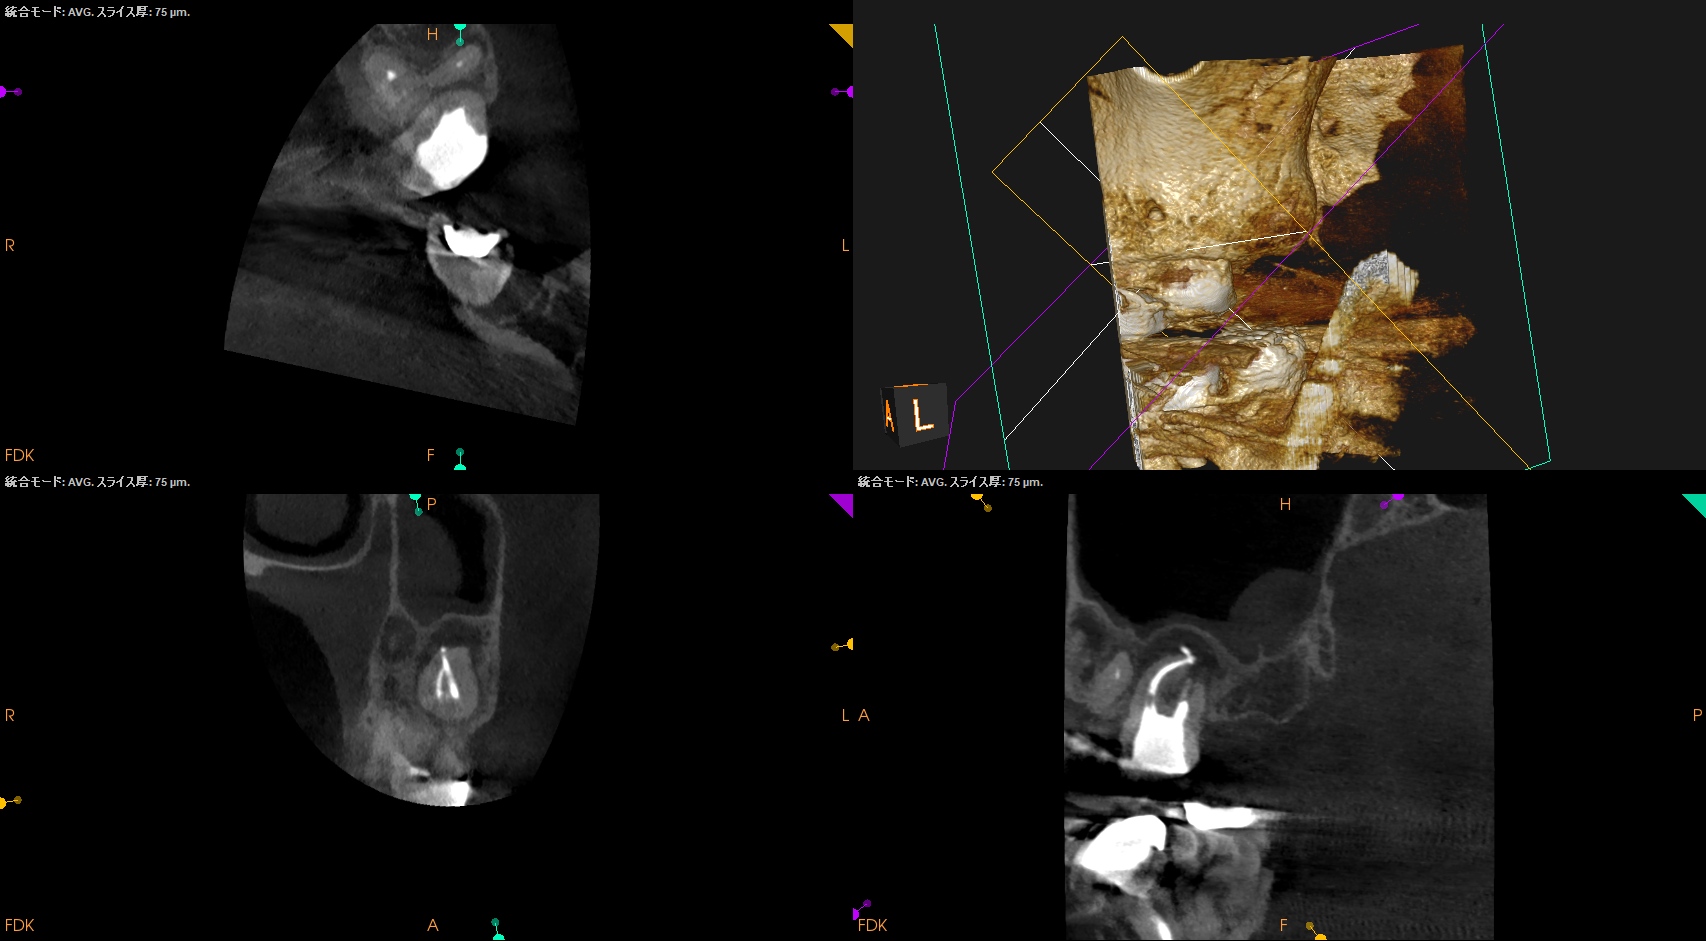

術後のPA, CBCTは以下である。

MB1

MB2

DB

P

問題はないだろう。